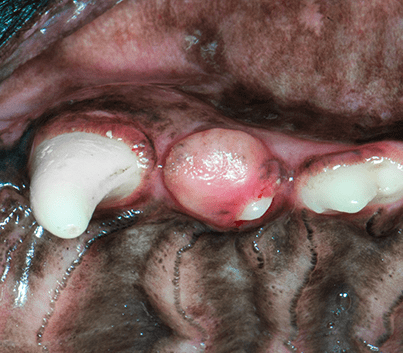

You may notice a distinct mass (tumor) or proliferation of tissue on your dog’s jaw or in his mouth. The most common area is at the front of the upper jaw. Masses start small but can continue to grow and become large. Acanthomatus ameloblastomas produce destruction of the underlying bone. This can cause a significant swelling in the region and also obvious pain. Your pet may exhibit signs such as excessive drooling, discomfort while eating or dropping of food, lack of appetite, difficulty closing and chattering of the jaw, or reluctance to be touched on the head.